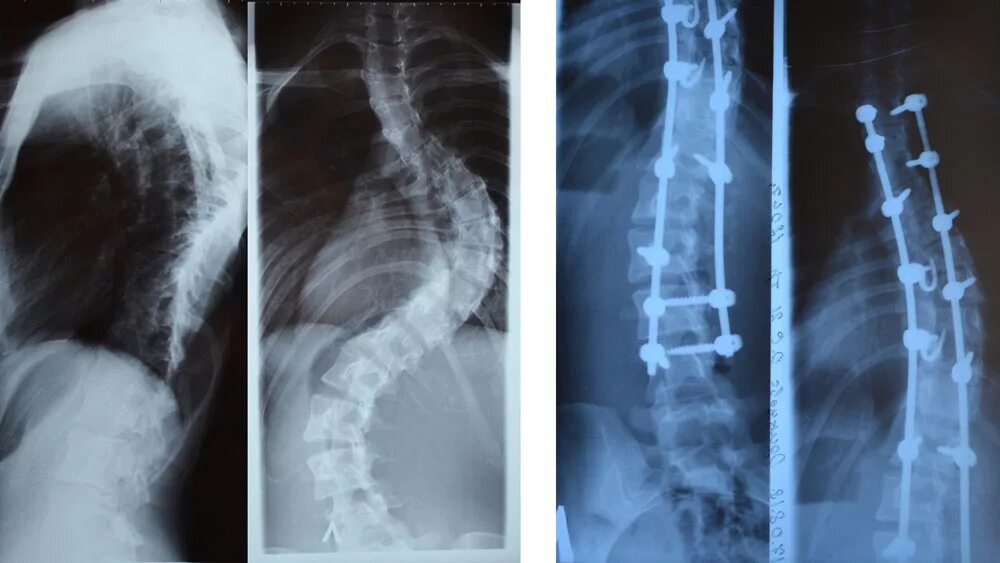

Сколиоз хирургия